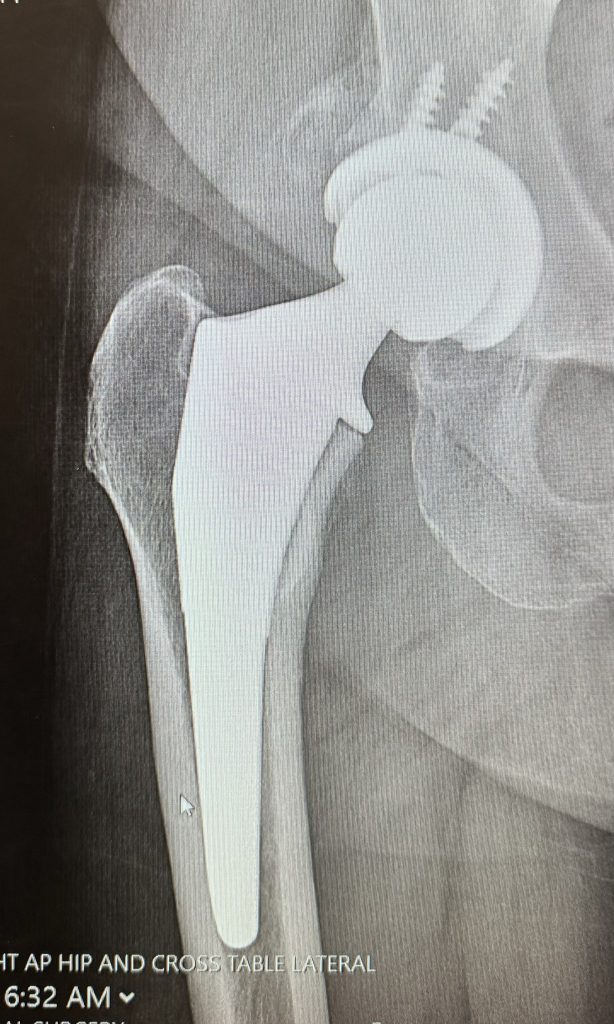

Exceptional (primarily female) team lead by Dr. Gausden. Everyone from the office assistant Samantha (very responsive, accommodating, kind) to the PAs to the anesthesiologist were engaged, smart, generous with their time and just had a wonderful optimistic energy that made me feel very good about the surgery. I felt like I was in exceptional hands throughout and I can't recommend Dr. Gausden and her whole team more highly. I think this image of my new joint is a great representation of the cheery attitude and calm demeanor of all involved.